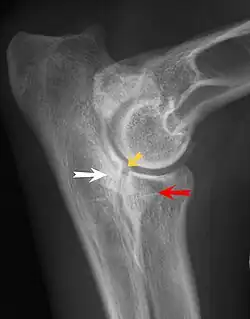

Most primary lesions are related to osteochondrosis, a disease of the joint cartilage, and osteochondritis dissecans (OCD), the separation of a flap of cartilage on the joint surface. Other common causes of elbow dysplasia include an ununited anconeal process (UAP) and fragmented or ununited medial coronoid process (FCP or FMCP).[1]

UAP is caused by a separation from the ulna of the ossification center of the anconeal process.[7] FMCP is caused by a failure of the coronoid process to unite with the ulna.

Diagnosis is through x-rays, arthroscopy or CT (computed tomography). In cases with significant lameness, surgery is the best option, especially with UAP. However, conservative treatment is often enough for cases of FMCP and OCD of the medial humeral epicondyle. The dogs are exercised regularly and given pain medication, and between the ages of 12 and 18 months the lameness will often improve or disappear.[4] Control of body weight is important in all cases of elbow dysplasia, and prevention of quick growth spurts in puppies may help to prevent the disease.